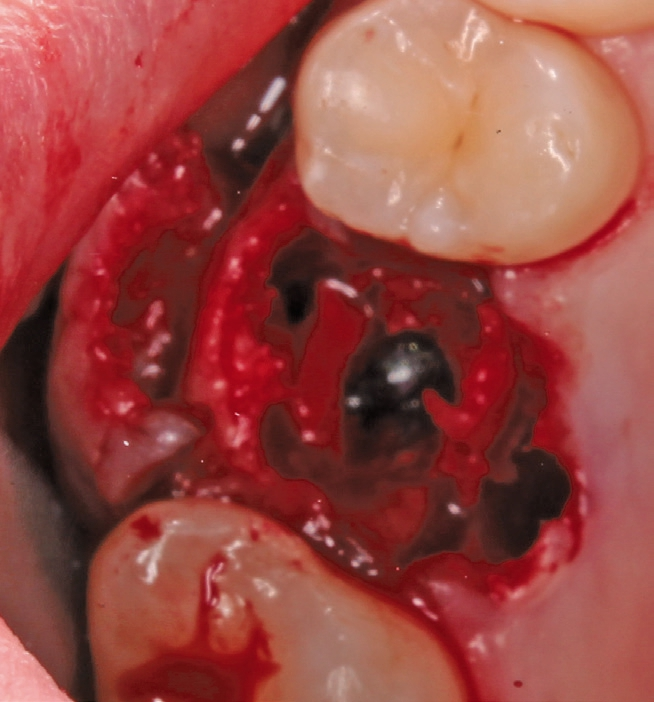

Ein 21-jähriger Patient stellte sich mit einer Perkussionsempfindlichkeit in regio 26 vor. Die klinische Untersuchung zeigte einen tiefzerstörten Zahn 26, dessen gesamte palatinale Wand tief fraktruiert war. Die Frakturgrenze verlief dabei weit unter dem palatinalen Zahnfleischrand (Abb. 1). Nach Erstellung eines Orthopantomogramms und einer radiologischen Einzelzahnbildaufnahme war eine längliche Verschattung am Apex der palatinalen Wurzel des Zahn 26 zu erkennen (Abb. 2), die den Verdacht einer überinstrumentierten Wurzelkanalaufbereitung der palatinalen Wurzel und einer Überstopfung des Füllmaterials bestätigte (Abb. 3). Nach konservierender Theapie wurde die Indikationsstellung für die Extraktion des Zahnes 26 mit einer Sofortimplantation gestellt. Der Periodontal-Screening-Index wies in allen Sextanten Grad 2 auf. Es folgte die Erstellung einer dreidimensionalen Röntgenaufnahme (Orthophos XG 3D, Dentsply Sirona, Bensheim) zur virtuellen Planung der Implantatposition. Die operative Planung erfolgte in der Planungssoftware coDiagnostiX 9.5 (dental wings, Montreal, Kanada) (Abb. 4).

Die Operation erfolgte in Lokalanästhesie (Ultracain® D/S forte, Aventis, Frankfurt) in Form einer Infiltrationsanästhesie bukkal und palatinal der Region 26. Mittels der Instrumentenspitze EXP4-L (Piezosurgery, Mectron, I-Genua) wurden die dentogingivalen Fasern vorsichtig durchtrennt und der Desmodontalspalt geweitet (Abb. 5 und 6). Nach Durchtrennung der Wurzeln wurde der Zahn mit einer Extraktionszange aus dem gelockerten Zahnfach vollständig entfernt (Abb. 7 und 8).